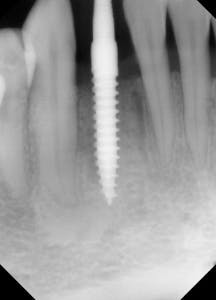

This is the case of a patient who has been missing a lower incisor for more than a year due to a failed root canal treatment (RCT). While there’s plenty of space mesiodistally, bone sounding helped us determine that there was only 4 mm of bone in the buccolingual dimension. A mini-implant was placed without raising a flap, the impression was taken at the time of surgery, and the implant was restored three weeks later.

Figure 1: Radiograph of pilot drill